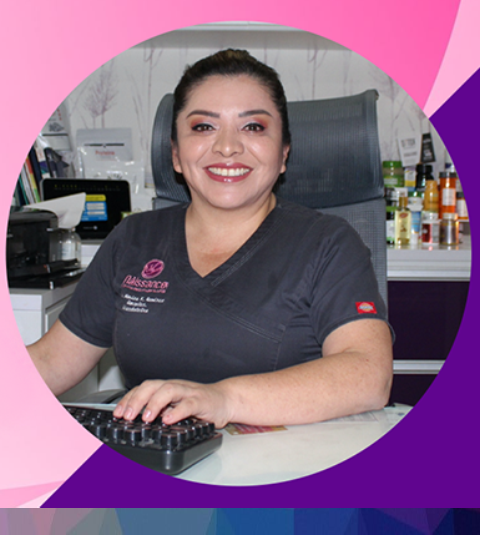

Dra. Mónica Karina Ramírez González

Certificado No. 7199 por la Federación Mexicana del Colegio de Obstetricia y Ginecología.